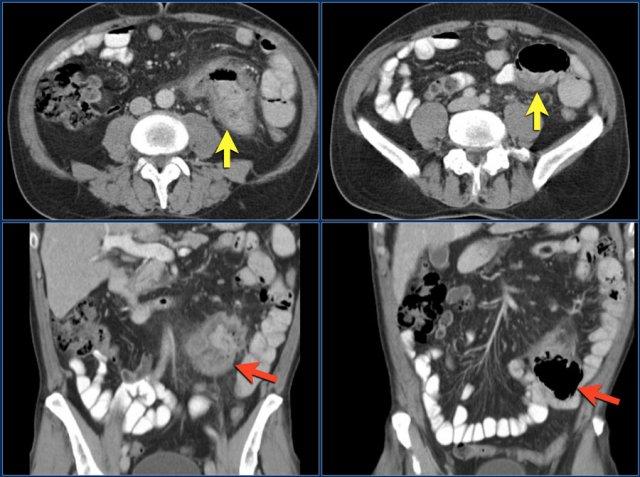

Các hình ảnh cho thấy một khối hình vòng ngắn gây tắc nghẽn ở hỗng tràng (mũi tên vàng) kèm hạch bạch huyết to (mũi tên đỏ).

Kết quả giải phẫu bệnh xác nhận là ung thư biểu mô tuyến.

Các dấu hiệu hình ảnh:

- Tổn thương gây tắc nghẽn ở hồi tràng với bờ dạng vai dẫn đến tắc ruột non (mũi tên vàng).

Có thể cân nhắc chẩn đoán bệnh Crohn.

Tuy nhiên bệnh nhân này không có tiền sử bệnh Crohn và hồi tràng tận (không hiển thị) bình thường, điều này sẽ không điển hình cho bệnh Crohn.

Kết quả phẫu thuật xác nhận đây là ung thư biểu mô tuyến.